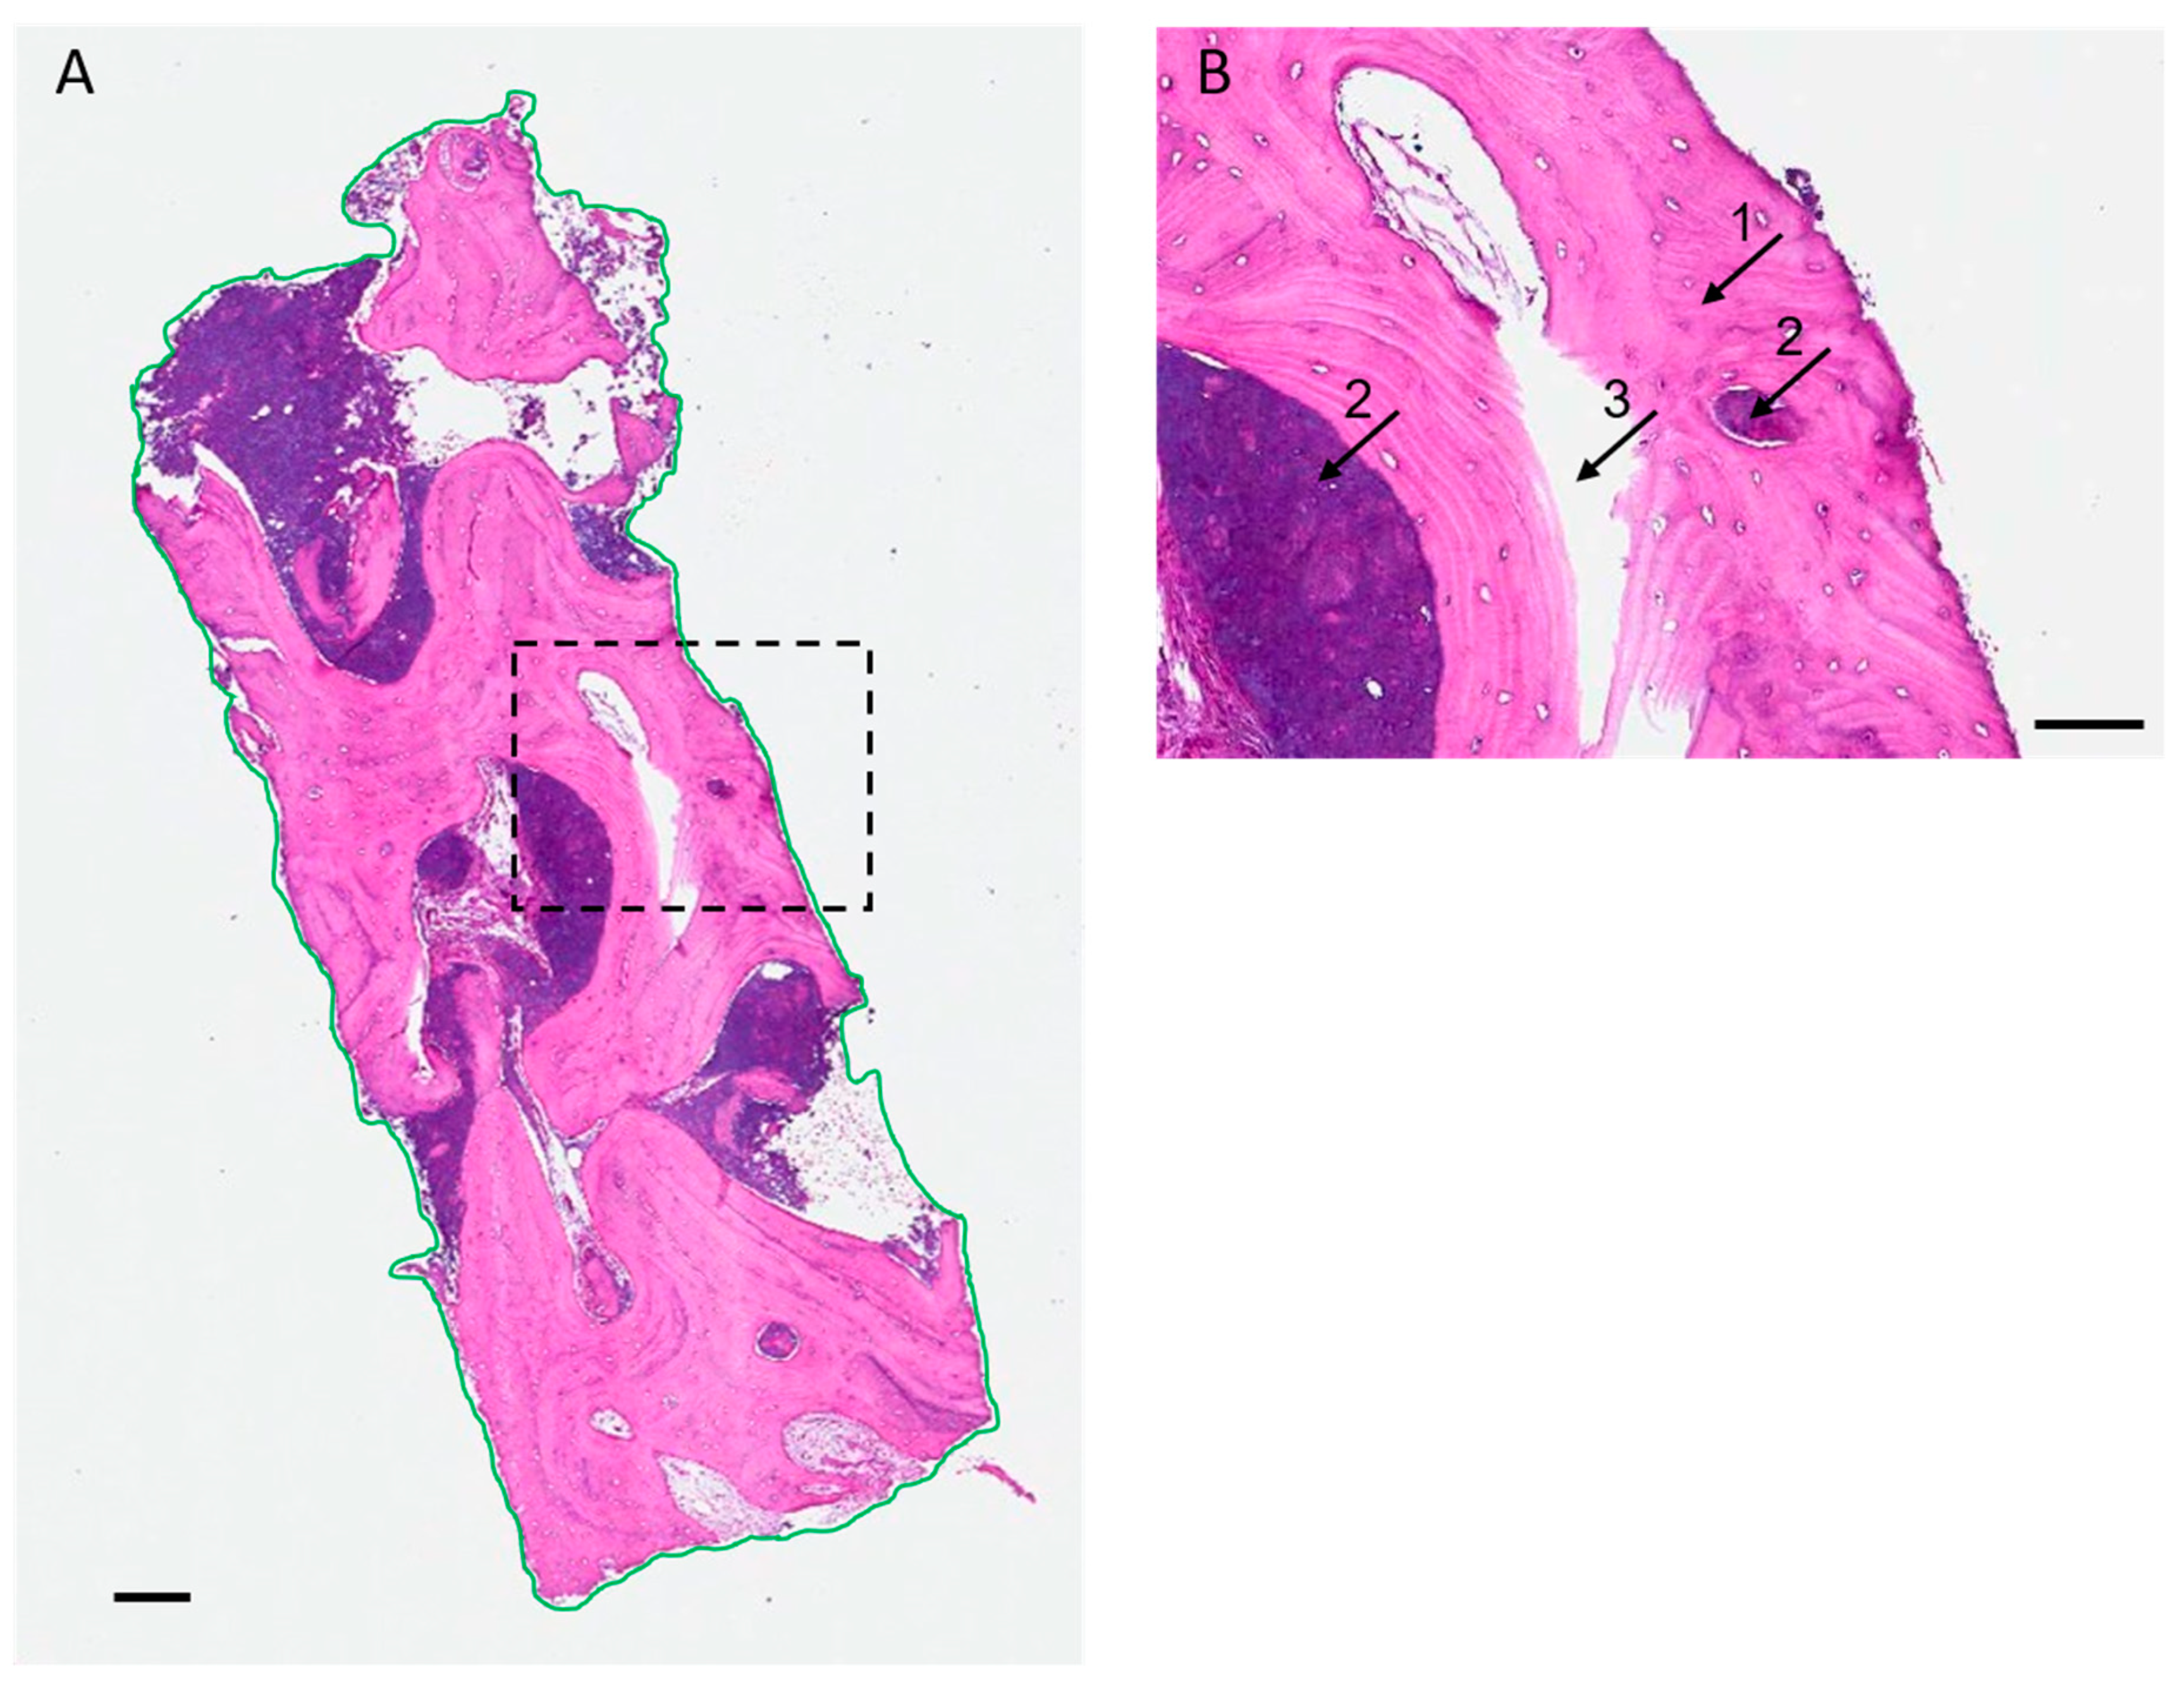

2.3. Histologic and Histomorphometric Analysis